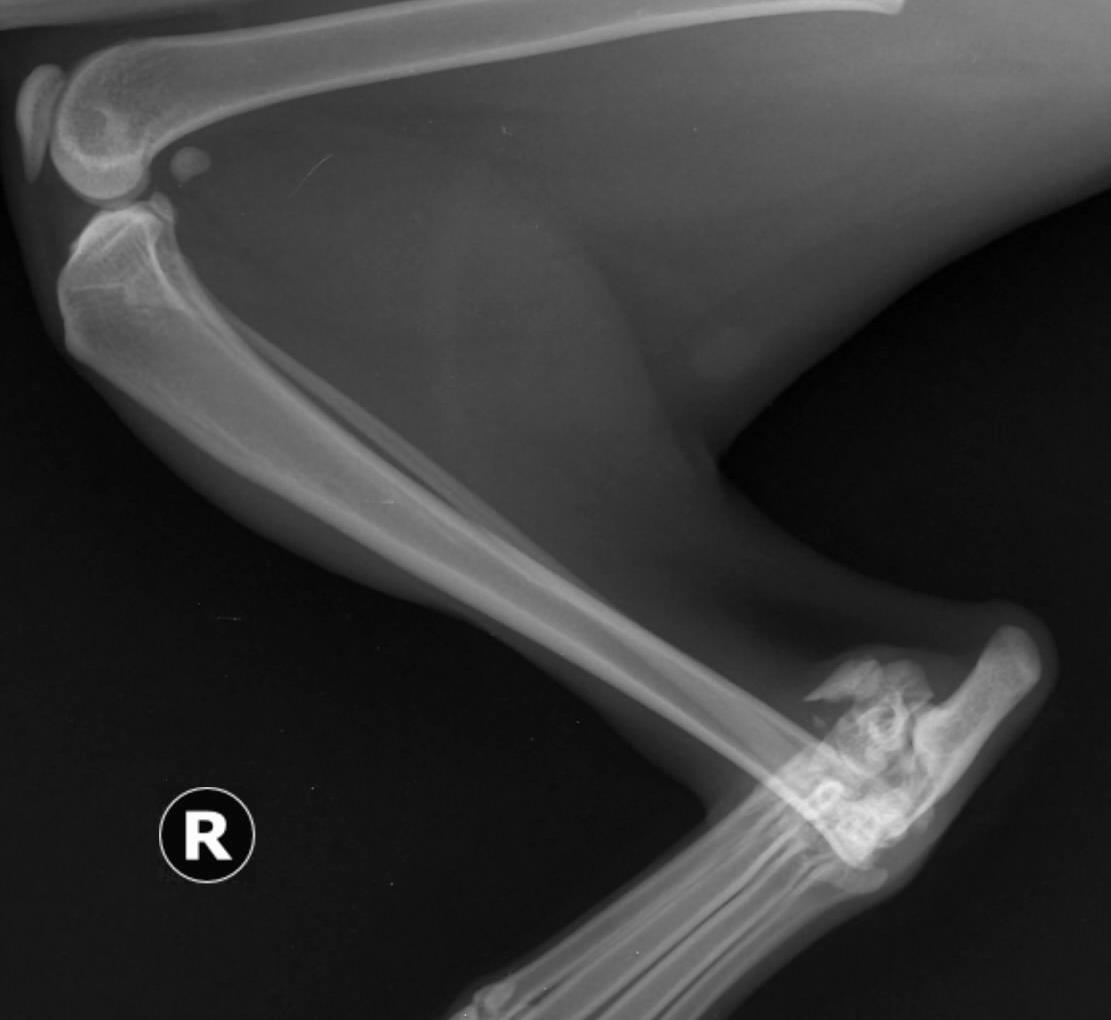

Validarea poziționării corecte a plăcii în raport cu osul și a selecției adecvate a dimensiunii și numărului șuruburilor s-a efectuat prin examenul imagistic radiografic convențional, utilizând incidențele clasice, medio-laterală și cranio-caudală (figura 21).

Investigațiile imagistice postintervenție au relevat integritatea articulația genunchiului și a articulației jaretului. Cartilajele articulare, epifizele și metafizele nu au suferit modificări. Amplasarea șuruburilor nu a modificat poziția fibulei, în raport cu tibia.

Figura 21. Imaginea radiografică a gambei după fixarea plăcii – incidență medio-laterală (a) și cranio-caudală (b)